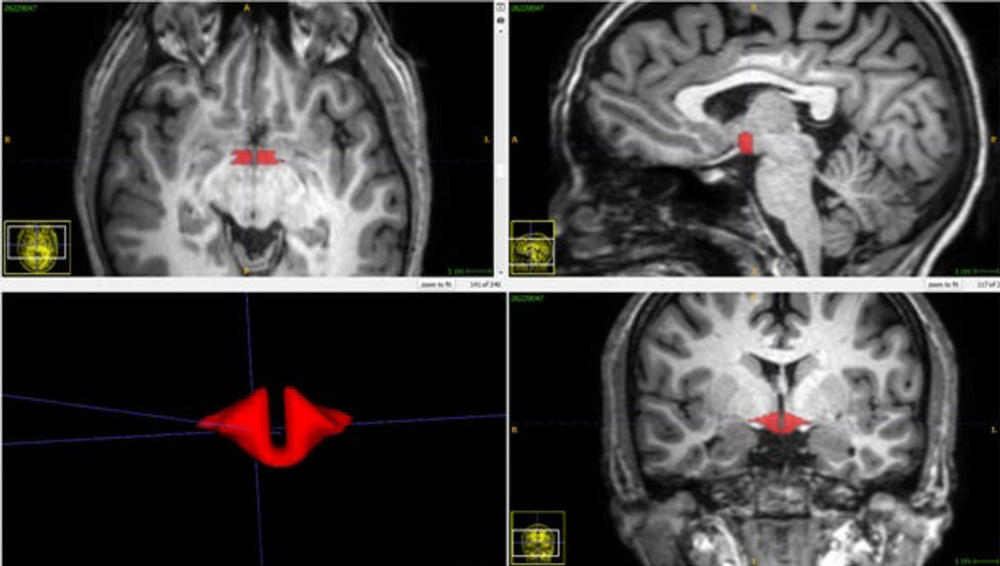

גלולות למניעת הריון גורמות לירידה בנפח של ההיפותלמוס במוח.

על פי החוקרים זהו המחקר הראשון שבדק את ההשפעות של אמצעי מניעה אוראליים על מבנה ההיפותלמוס האנושי ושמצא שלנשים הנוטלות גלולות למניעת הריון נפח ההיפותלמוס קטן משמעותית לעומת אלו שלא לקחו את הגלולות. מחקר ראשוני זה מראה קשר חזק ואמור להניע חקירה נוספת לגבי ההשפעות של אמצעי מניעה אוראליים על מבנה המוח והשפעתם הפוטנציאלית על תפקוד המוח.

החוקרים מסבירים שההיפותלמוס אחראי בין היתר על תיאבון, מצבי רוח, טמפרטורת גוף, תבניות שינה, חשק מיני, דופק לב וכמו כן מעורב בתהליכי ייצור של הורמונים חיוניים. כמו כן נמצא שהיפותלמוס קטן קשור למצבי דיכאון וגם התקפי זעם.